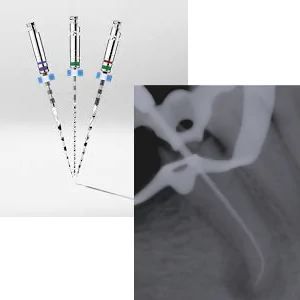

Ni-Tiファイル

従来はステンレス製のヤスリ状の物を用いていましたが、このファイルは柔らかく、曲がった根管などに対しても対応でき、治療時間の短縮にも繋がります。